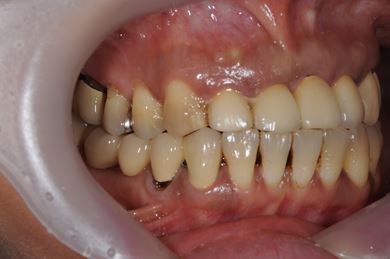

インプラントの症例写真 IMPLANT

抜歯即日スピードインプラント治療

| 性別/年齢 | 女性 / 44歳 | ||||||||||||||||||||||||||||||||

| 主訴 | 上のさし歯がグラグラする。インプラントにした方が良いのか、相談したい。 | ||||||||||||||||||||||||||||||||

| 治療方針 | 抜歯と同時にインプラントを埋入し、治療期間を短縮する。 | ||||||||||||||||||||||||||||||||

| 治療内容 | インプラント2本(抜歯即日スピードインプラント)、メタルボンドセラミック2本 | ||||||||||||||||||||||||||||||||

| 総治療費 | 458,588円 | ||||||||||||||||||||||||||||||||

| 治療期間 | 6ヶ月 |